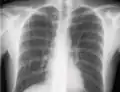

La incidencia de neumotórax es mayor con el cateterismo de la vena subclavia debido a su proximidad anatómica al ápice del pulmón. En el caso de la cateterización de la vena yugular interna, el riesgo de neumotórax se minimiza mediante el uso de guía ecográfica. Para los médicos experimentados, la incidencia de neumotórax es de aproximadamente 1.5 a 3.1%. El Instituto Nacional de Salud y Excelencia Clínica (Reino Unido) y otras organizaciones médicas recomiendan el uso rutinario de la ecografía para minimizar las complicaciones.[5]

Si se sospecha un neumotórax, se debe obtener una radiografía de tórax en posición vertical del paciente. Se prefiere una radiografía de tórax en posición vertical porque el aire libre migrará al vértice del pulmón, donde se visualiza fácilmente. Por supuesto, esto no siempre es posible, especialmente en pacientes críticamente enfermos en la unidad de cuidados intensivos. Las radiografías obtenidas en decúbito supino no detectan entre el 25 y el 50% de los neumotórax.[6] Sin embargo, la ecografía puede usarse como método de detección en personas demasiado enfermas para obtener imágenes en posición vertical.[3]